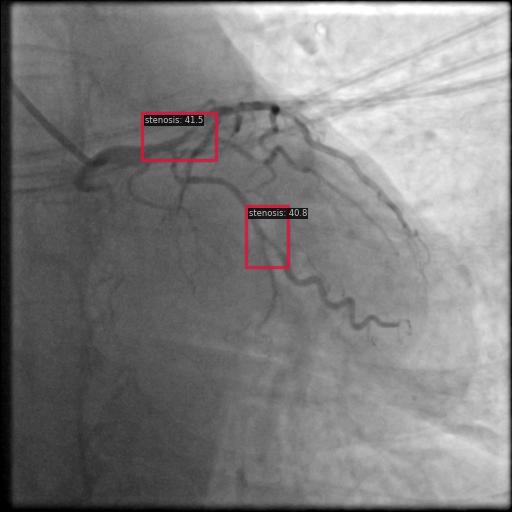

To further assess the detection performance, qualitative results for three test images are presented in Figure 2. The first column shows the original images with ground truth annotations. The second, third, and fourth columns depict detections from DINO-DETR, Grounding DINO, and YOLO, respectively.

(a) Original (b) DINO-DETR (c) Grounding DINO (d) YOLO

The qualitative comparison in Figure 2 reinforces the trends observed in the quantitative evaluation. DINO-DETR produced fewer detections, occasionally missing relevant stenotic regions, consistent with its conservative detection strategy aimed at minimizing false positives [6]. Grounding DINO, although capable of identifying more regions, sometimes resulted in cluttered predictions due to over-detections [7]. YOLO provided a reasonable trade-off by effectively capturing anatomical structures while maintaining relatively high confidence scores and clear visualizations [5].